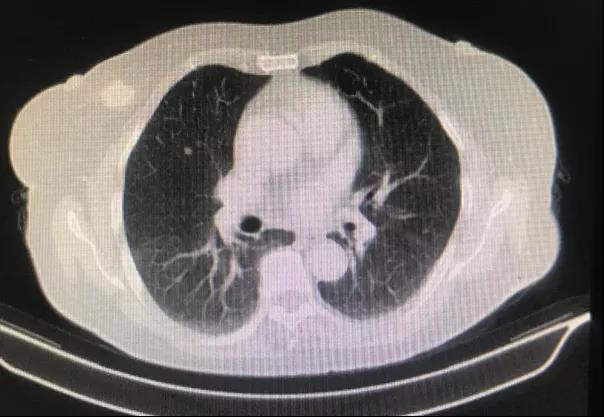

乳腺超声:右乳1-2点乳晕处探及低回声,大小约3.5 cm x 1.6 cm。肝脏超声:肝内转移瘤,最大位于肝右后叶,约5.0 cm x 3.8 cm。胸腹部CT:右乳内上象限结节,大小约2.0 cm x 1.8 cm,分叶状,边缘多发毛刺,考虑恶性。双肺多发结节,大者约0.5 cm x 0.5 cm,考虑转移。肝脏内多发结节,大者约4.5 cm x 3.9 cm,考虑转移。PET-CT检查:右乳恶性结节,约1.9 cm x 1.7 cm,双肺多发转移结节,大者约0.6 cm x 0.5 cm,肝脏多发转移结节,大者约5.0 cm x 4.6 cm。

一线内分泌治疗进展后,换用化疗。于2019年7月至2020年5月期间接受口服长春瑞滨单药50mg 每周三次治疗,共用药11个月。毒副作用评估,表现为Ⅰ度骨髓抑制。疗效评价:最佳疗效SD,PFS 11个月;CT评估:乳腺病灶2.6 cm → 2.7 cm → 3.5 cm;肺转移灶0.7 cm → 0.7 cm → 1.3 cm;肝转移灶4.0 cm → 3.1 cm → 4.5 cm。